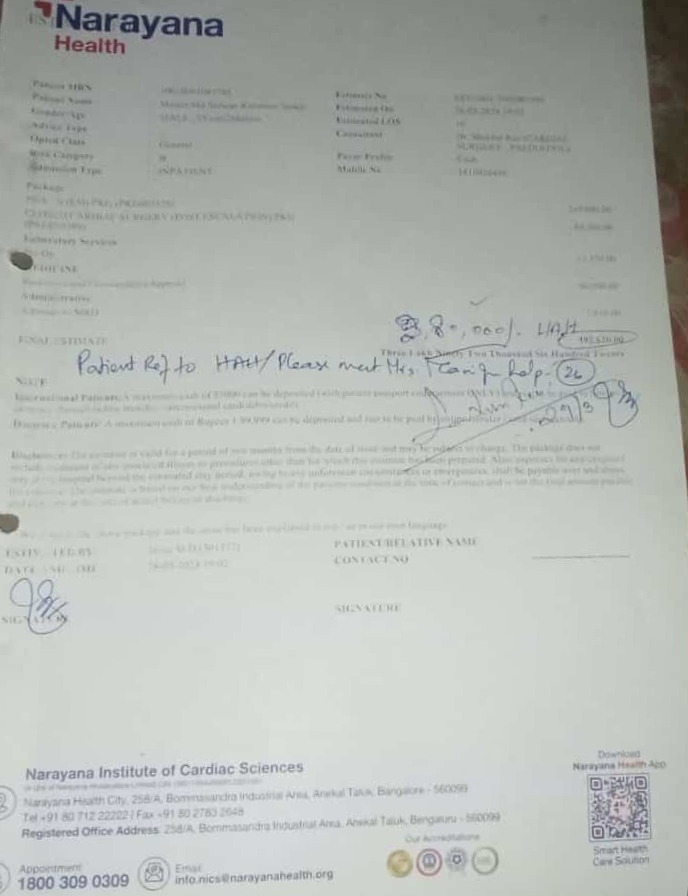

#250928C: ছোট্ট বাচ্চা সাফওয়ান রহমান সৈকতের হার্টের ছিদ্র এবং রক্তনালীর ছিদ্রের অপারেশনের জন্য সাহায্যের আবেদন; গ্রাম:আড়ালিয়া, জেলা: জামালপুর।